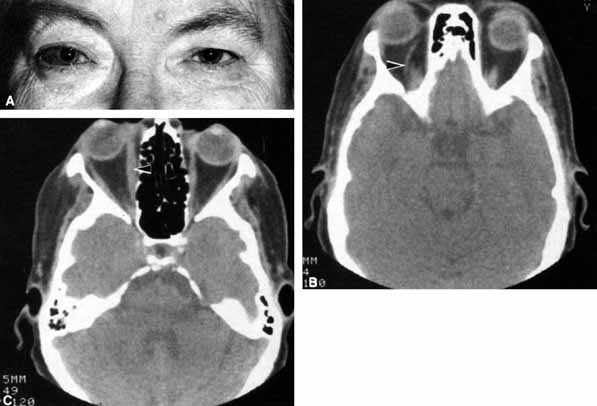

CASE 1

A 70-year-old woman presented with a 6-month history of progressive diplopia and ptosis. She demonstrated complete right third, fourth, and sixth cranial nerve palsies, and hypesthesia of cranial nerve V1 (Fig. 22A). The right pupil was dilated. Computed tomography (CT) disclosed an intracavernous aneurysm (see Fig. 22B).

Fig. 22 A. A 70-year-old woman with complete right third, fourth, and sixth cranial nerve palsies. Hypesthesia of cranial nerve V1 was also present. B. CT scan demonstrates an intracavernous aneurysm (arrow).

The so-called superior orbital fissure syndrome occurs when an infiltrative, inflammatory, or ischemic event occurs within the superior orbital fissure, but not in the orbital apex.4 A complete superior orbital fissure syndrome occurs when all the neurovascular components passing through the superior orbital fissure are damaged, producing a total ophthalmoplegia, ptosis, and anesthesia of cranial nerve V1 (see Fig. 22A). The pupil may be dilated, miotic, or midposition and fixed, depending on the balance of parasympathetic and sympathetic damage. The superior ophthalmic vein, best seen on CT, may be dilated if venous outflow from the orbit is obstructed. Clues to venous outflow obstruction are increased intraocular pressure, fullness of the upper eyelid, and hyperemia of the deep Tenon's vessels. Ophthalmoscopically, the retinal veins may be dilated. The effect of a lesion in the superior orbital fissure or the anterior cavernous sinus cannot be differentiated clinically (see Fig. 22B). When the posterior cavernous sinus becomes involved, hypesthesia of cranial nerve V2 may also be present.

The only difference between a superior orbital fissure syndrome and an orbital apex syndrome is the presence of visual loss caused by optic nerve involvement. Visual acuity, color vision, or the visual field are abnormal. An ipsilateral relative afferent pupil defect is present.